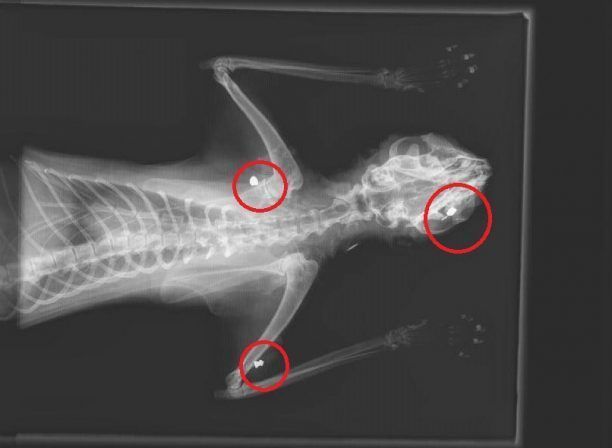

Το εγκληματικό του έργο συνεχίζει ο παράφρονας που συστηματικά πυροβολεί γάτες στο Γαλάτσι καθώς σήμερα το νεοσύστατο φιλοζωικό σωματείο της περιοχής «Γαλατσιώτικες Αδέσποτες Φάτσες!» ενημερώθηκε ότι στις 10 Νοεμβρίου 2015 μια ακόμα γάτα εντοπίστηκε να κείτεται στην οδό Νάξου και οι ακτινογραφίες έδειξαν τα πέντε σφαιρίδια του αεροβόλου στο κορμί της.

GalatsiGataPyrovolimeniAerovolo11-2015 (2)Βρέθηκε στην οδό Νάξου στις 10 Νοεμβρίου 2015.